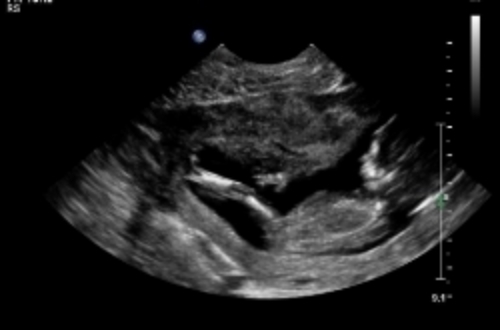

and a potty shot which i know isn't really accurate at this point

she actually posted her own thread LOL. Possibly boy. Potty shot isnt viable at 13/6